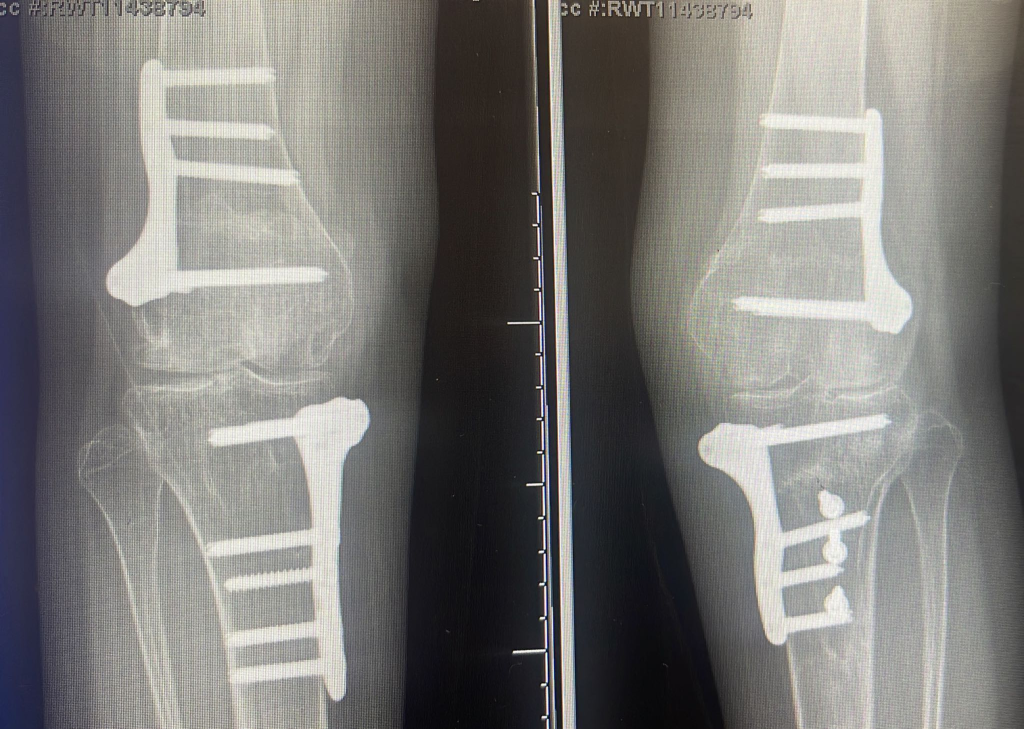

Tibial osteotomy - (5-50)

Removal of internal fixation from bone / joint, excluding K-wires +/- image guidance - (1-5)